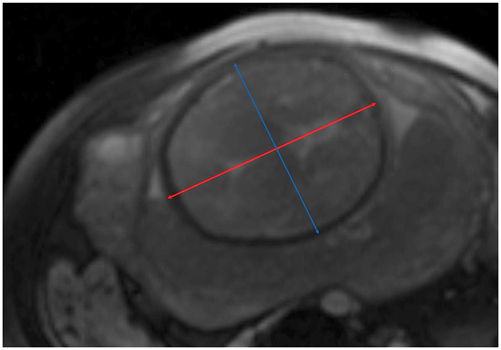

Intertubal distance, pubic angle, obstetric and true conjugate, and fetal biparietal and occipitofrontal diameters were measured by an experienced radiologist (8 years experience in urogenital imaging) (see Figures 2 and 3). The type of breech, e.g. complete, incomplete or Frank breech, was described as well as placental position and possible maternal pathologies. In addition, all studies were reviewed by a consultant paediatric radiologist.

Fetometry of the head. Axial view of the fetal head, measurement of biparietal (blue double arrow) and occipitofrontal diameter (red double arrow) at the level of the thalami and cavum septi pellucidi.